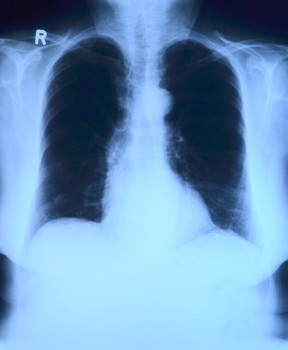

X-thorax bij verdenking pneumonie

Nieuw onderzoek toont aan dat huisartsen die een patiënt verdenken van een pneumonie hierin vaak worden bevestigd met een röntgenfoto. Hoe sterker de huisarts een longontsteking vermoedt, hoe vaker er een pneumonie wordt aangetroffen.

In een Zweeds prospectief onderzoek van Moberg et al. is in de eerste lijn onderzoek gedaan bij 103 patiënten bij wie de werkdiagnose pneumonie gesteld was. Bij deze patiënten werd een anamnese verricht, lichamelijk onderzoek gedaan en bloedmonster afgenomen (zowel leukocyten, als leukocyten differentiatie en POC (point of care) CRP). Daarna werd er zo snel mogelijk een thoraxfoto gemaakt. Deze foto werd niet gebruikt om het beleid te bepalen maar om te kijken of de door de huisarts gestelde diagnose radiologisch bevestigd kon worden.

Hieruit bleek dat afwijkingen bij auscultatie, koorts en een verhoogd CRP samenhingen met een radiologisch bewezen pneumonie. Echter in de analyse waar alle mogelijke variabelen tegelijk getest werden, bleek alleen nog het CRP gerelateerd: OR 10,9 (95%-BI 3,0 tot 39,2). De opmerkelijkste bevinding was dat een sterk vermoeden van de huisarts op een longontsteking erg vaak (in 88%) gerelateerd was aan een daadwerkelijke, radiologisch bewezen longontsteking.